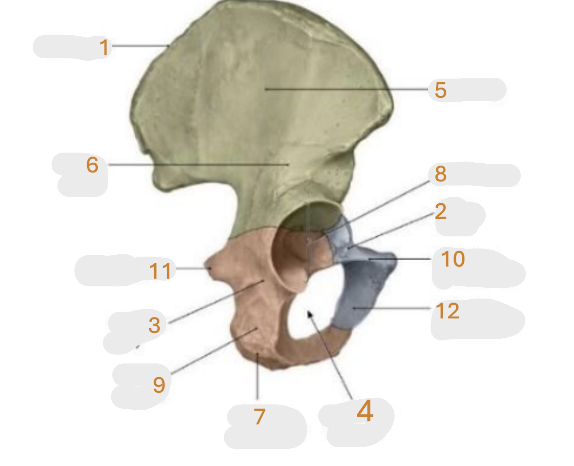

Where is the iliac crest

1

Where is the pectineal line

2

Where is the posterior iliac spine

3

Where is the iliac fossa

4

Where is the ischial tuberosity

5

Where is the iliac tuberosity

6

Where is the anterior superior iliac spine

7

Where is the obturator foramen

8

Where is the auricular surface of the ilium

9

Where is the anterior inferior iliac spine

10

Where is the ilium body

11

Where is the ischial ramus

12

Where is the arcuate line

13

Where is the pubic tubercle

14

Where is the ischium body

15

Where is the inferior pubic ramus

16

Posterior superior iliac spine

17

Where is the symphyseal surface

18

Where is the pubis body

19

Where is the superior pubic ramus

20

Where is the ischium body

21